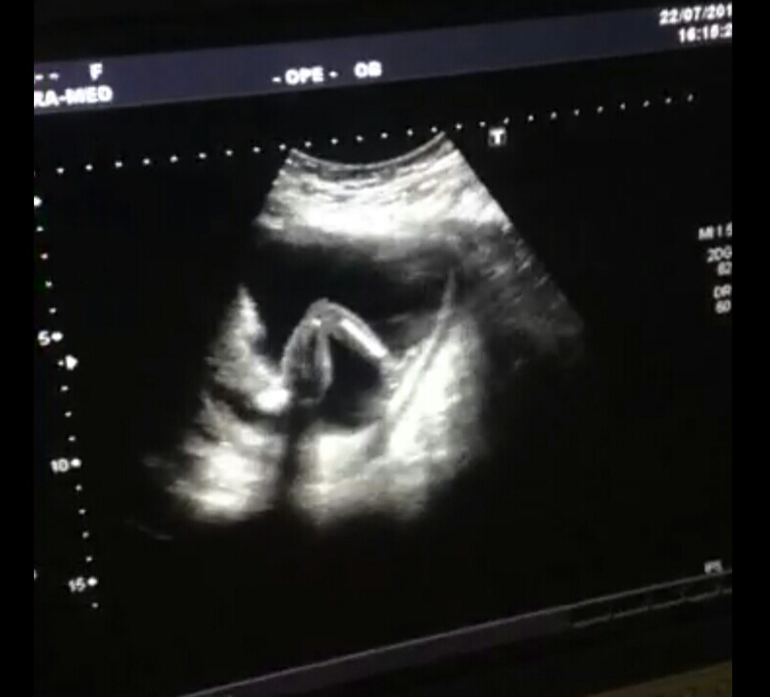

Ручкой за носик хватался) и ножки показали)

Поздравляю!! :) Я всегда думала, что снимки УЗИ у всех одинаковые, но смотрю на ваши фотографии, все-таки нет, видно очертания личика) У нас носик другой и губки) прикольно)